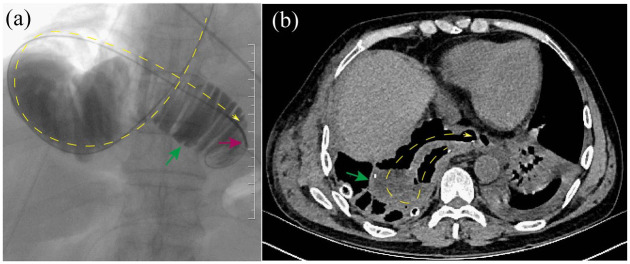

近年来,食管切除术后常见的术后并发症越来越受到重视。然而,对罕见并发症的关注还不够,这些并发症如果不及时诊断往往会导致严重后果。在这篇文章中,我们将介绍食管切除术后罕见并发症的临床和影像学特征,以及预防和处理这些并发症的策略。这些罕见的并发症分为四组:食管代用品相关并发症、胸导管相关并发症、疝气相关并发症和经壁Hem-o-lok夹移位。食管代用品相关并发症包括多余的导管和导管坏死。我们进一步将冗余管道分类为长度冗余管道,宽度冗余管道或两种冗余的组合。胸导管相关并发症包括难治性乳糜胸和乳糜纵隔。难治性乳糜胸是一种建立良好的医学、介入甚至外科治疗策略都难以治疗的乳糜胸,而乳糜纵隔是一种罕见的疾病,其特征是乳糜在纵隔积聚。疝相关并发症可分为裂孔疝、心后肺疝、肋间肺疝、套管针部位疝、胸骨后间隙或心包内疝和肠系膜缺损。经壁Hem-o-lok夹移动包括穿透气管、导管或两者。胸外科医生应熟悉食管切除术的罕见并发症,这些并发症大多是严重的,需要早期准确诊断并妥善处理。对罕见并发症的干预选择取决于患者的一般情况、并发症的具体类型、并发症的严重程度、重建途径、可用的医疗资源和外科医生的偏好等因素。为了将这些并发症的风险降到最低,食管切除术和预防方法需要标准化。

In recent years, common postoperative complications after esophagectomy have received increasing attention. However, the attention paid to rare complications, which often lead to serious consequences if they are not diagnosed in a timely manner, has not been sufficient. In this article, we present both the clinical and imaging features of rare complications following esophagectomy and strategies for their prevention and management. These rare complications are classified into four groups: esophageal substitute-related complications, thoracic duct-related complications, hernia-related complications, and transmural Hem-o-lok clip migration. Esophageal substitute-related complications include redundant conduits and conduit necrosis. We further classify redundant conduits as length-redundant conduits, width-redundant conduits, or a combination of both redundancies. Thoracic duct-related complications include refractory chylothorax and chylomediastinum. Refractory chylothorax is chylothorax refractory to well-established medical, interventional, and even surgical strategies, whereas chylomediastinum is a rare condition characterized by the accumulation of chyle in the mediastinum. Hernia-related complications are subclassified as hiatal hernias, retrocardiac lung hernias, intercostal lung hernias, trocar-site hernias, hernias internal to the retrosternal space or pericardium, and mesenteric defects. Transmural Hem-o-lok clip migration includes penetration of the trachea, conduit, or both. Thoracic surgeons should familiarize themselves with the rare complications of esophagectomy, most of which are serious conditions that require early and accurate diagnosis for proper management. The choice of intervention for rare complications depends on factors such as the patient's general condition, the specific type of complication, the complication severity, the reconstruction route, the available medical resources, and the surgeon's preference. To minimize the risk of these complications, esophagectomy and prevention methods need to be standardized.